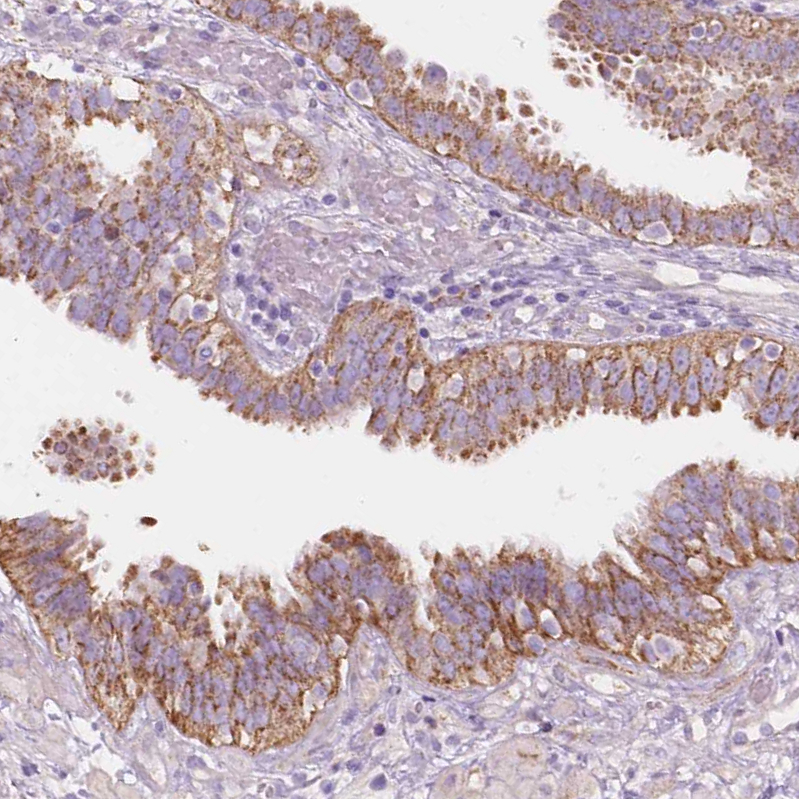

Immunohistochemical staining of human hippocampus shows moderate cytoplasmic positivity in neurons.